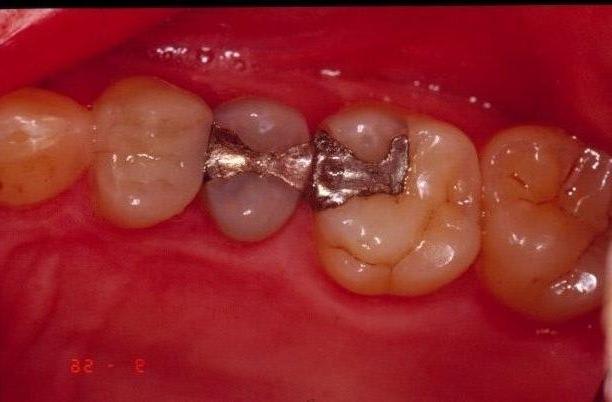

Je ne vois pas à part un petit sillon en vestibulaire où l'onlay est mal ajusté ?

Tiens Dudule , ce que moi je vois comme défauts d'adaptation.

Les bactéries pour la récidive n'ont pas de téléobjectif !!!!!

En vestibulaire ok, je l'ai même dit au départ... pour le reste je suis absolument pas d'accord (surtout en lingual où l'adaptation est top). Je n'ai par contre pas poli le joint après avoir retiré les excès (quelle infamie...).

C'est sur que le superbond étant translucide, on voit une différence de teinte au niveau du joint plus importante qu'avec des collages dual.

Comment peut-on juger de l'ajustage de la restauration sur une photo comme çà, restons sérieux.

lui mm trouve le joint vestibulaire mediocre, je trouve le resultat esthetique mediocre.

l esthetique aurait été ameliorée en englobant les cuspides, ça evitait le raccord au flow qui fait qd mm desordre ( qu'est ce qui se passe si ton flow se barre? donc toute ta reconstruction ceram top level depend d'un flow qui est qd mm pas le materiau qui vieillit le mieux et dont l'etancheité est rassurante ) ça eliminait les risque de fractures.

Premièrement je n'ai jamais dit que c'était mon premier onaly, juste que j'en avais pas fait à la fac. Deuxièmement, ça fait 10 minutes que je fais joujou avec mon ordi (constraste luminosité), tu dois avoir des yeux bionic car je ne voyais rien en bouche et je ne vois toujours pas où il y a un défaut d'étanchéité à part le sillon entre les 2 cuspides vest et l'onlay... mais bon je dois être très très mauvais. Troisièmement mon choix qui n'était peut-être pas le plus judicieux de ne pas toucher ces fameuses cuspides vestibulaires vient du fait que j'avais peur de rendre une dent symptomatique alors qu'elle ne l'était absolument pas malgré la carie pré-op et d'autre part que l'anatomie fait arriver le point de contact de la cuspide antagoniste sur l'onlay et pas sur la dent. Cherchant évidemment à progresser (sinon j'aurai pas posté), pourriez vous me posté des photos de joint avec superbond parceque moi j'ai à chaque fois cet aspect translucide fin à la jonction de mes collages. Ce post aura au moins eu le mérite de permettre un débat et c'était là mon but sur préservation vitalité ou non. (car je continue à ne pas voir où est le mauvais ajustage).